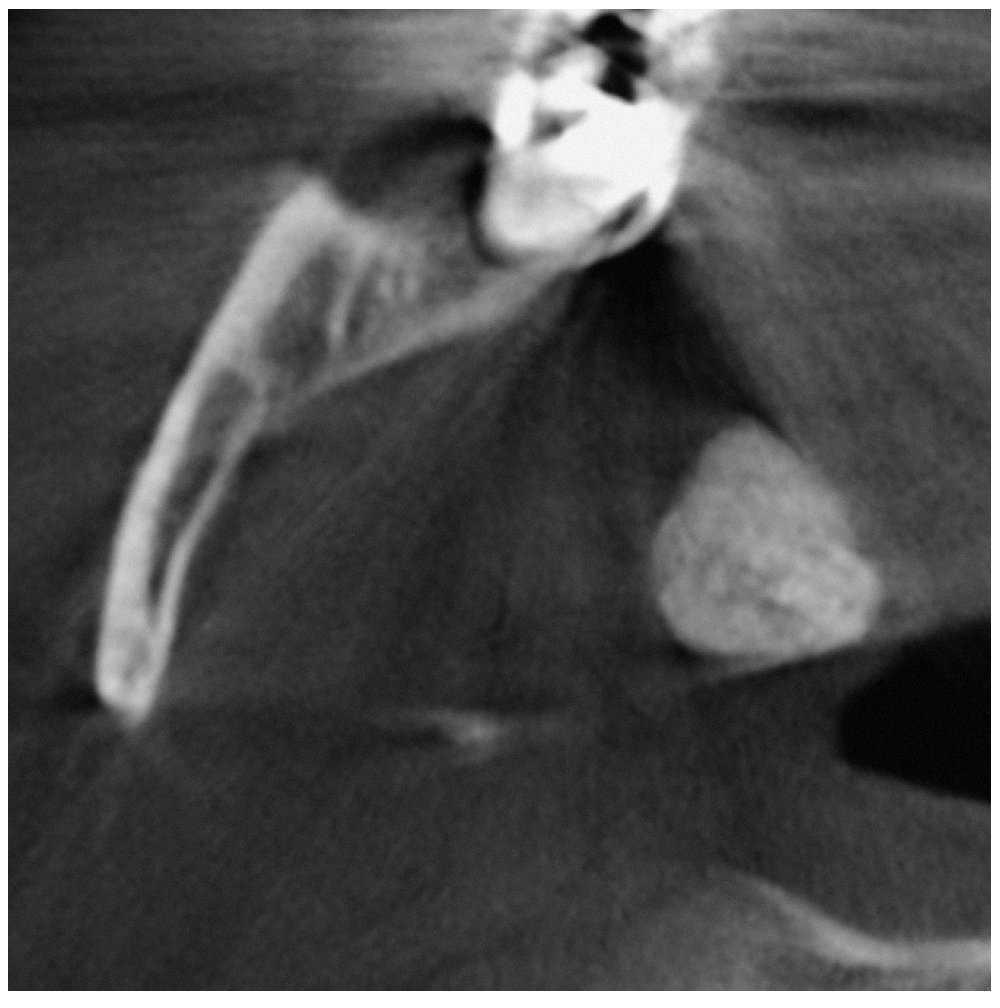

Se obtuvo una tomografía volumétrica digital dental para completar el estudio diagnóstico. En la tomografía destacó a 1,5 cm en medial de la rama mandibular derecha una masa redondo-ovalada, hiperdensa y bien delimitada con un tamaño de aproximadamente 12 x 10 mm localizada en los tejidos blandos parafaríngeos (figs. 2 a 4). De este modo se descartó con certeza la presencia de un sialolito.

Figura 3. Tomografía volumétrica digital dental: plano coronal.

En la faringe existen diversos «islotes» de tejido linfático que se denominan amígdalas o tonsilas. Las zonas parafaríngeas de las mismas corresponden a las amígdalas palatinas. Las infecciones recidivantes de las vías respiratorias altas (bronquitis, laringitis) pueden provocar abscesos crípticos en el tejido linfático que, más adelante, pueden calcificarse. Como resultado de su ubicación, en las radiografías se suelen proyectar sobre la rama mandibular y se visualizan a menudo como imágenes radioopacas de pequeño tamaño parecidas a salpicaduras calcáreas. Por el contrario, las calcificaciones de mayor tamaño, como las de este caso clínico, son más bien raras y suelen corresponder a un cálculo amigdalino o tonsilolito.